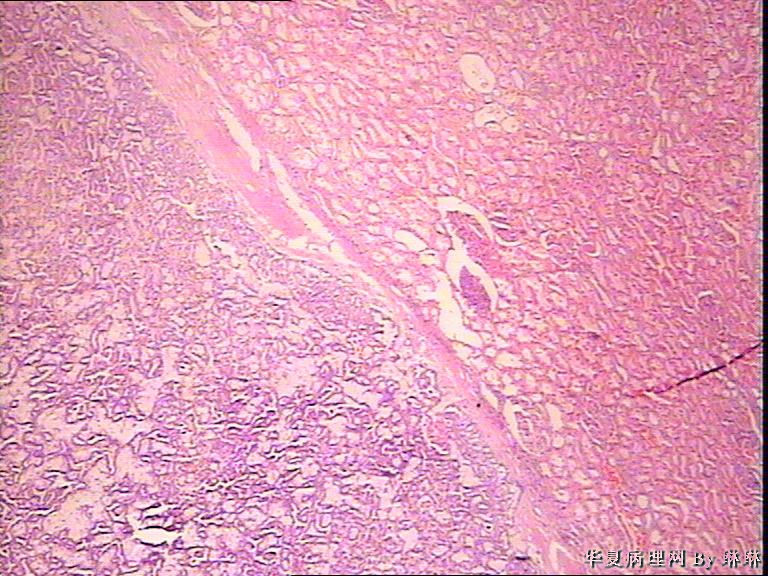

患者男性,50岁,右肾外伤可见一淡黄色圆形肿物,包膜完整,部分突出于肾表面,直径约3.5cm,切面淡黄色,质软。请各位看看,多多发表见解。

仔细看看有没有乳头状结构,要先考虑乳头状肾细胞癌,1 型。

考虑乳头状肾细胞癌

感觉还像透明细胞肾癌。

乳头状肾细胞癌